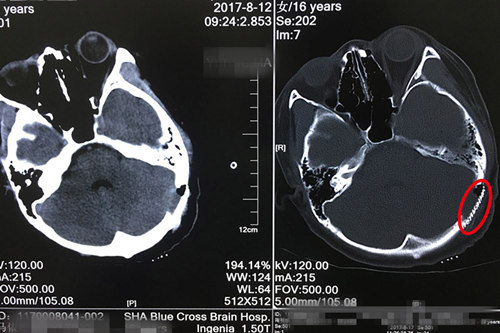

术后CT显示:钛网与颅骨结合紧密,未见明显异常病灶。